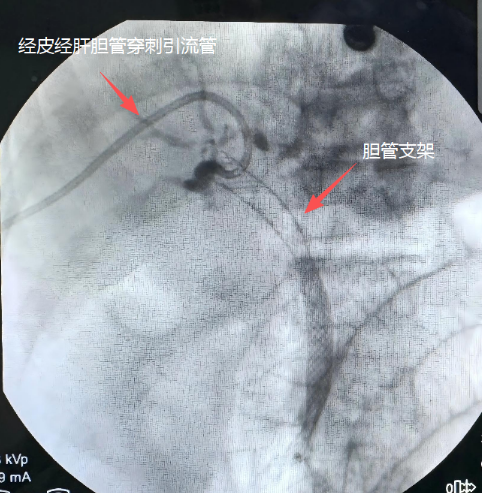

胆石病医院介入团队先经皮经肝穿刺进入扩张的肝胆管,尝试将导丝自上而下顺行通过梗阻段。经过多次超选后,导丝竟顺利通过狭窄的肿瘤段,内镜团队在肠道内同步接应,成功“会师”,建立贯通通道,并顺利植入金属支架。支架释放后,胆道立即恢复通畅,淤滞已久的黑褐色胆汁顺利流入肠道,成功实现内引流。

胆管支架和经皮经肝胆管穿刺引流管示意图。通讯员供图